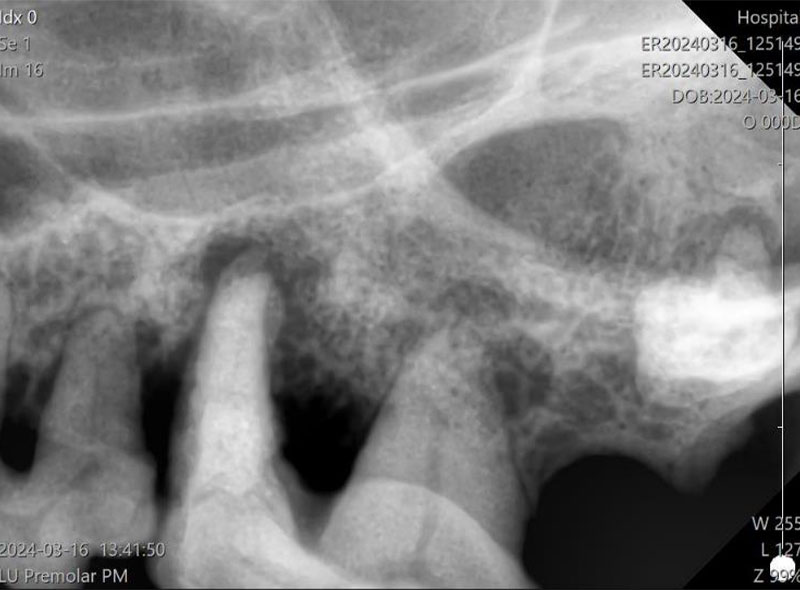

レントゲン撮影

歯科レントゲンにより、歯槽骨の状態を評価します。